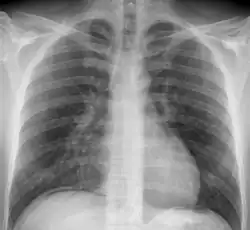

Objawem radiologicznym perforacji przewodu pokarmowego jest obecność wolnego gazu pod przeponą, który na zdjęciu jest widoczny jako przejaśnienie o kształcie sierpa lub rogala[10]. Powietrze zgromadzone pod kopułą przepony powoduje również zniesienie stłumienia wątrobowego podczas opukiwania jamy brzusznej[11]. W tomografii komputerowej widoczne jest wolne powietrze, wolny płyn poza światłem uszkodzonego narządu, nieciągłość ścian narządu, wyciek kontrastu lub obecność zmian zapalnych. TK pozwala dokładnie określić miejsce perforacji[12], jest szczególnie przydatna w diagnostyce "ukrytej perforacji" oraz "zamkniętej perforacji"[13]. Perforacja w obrębie klatki piersiowej (przełyk) w badaniu radiologicznym jest widoczna jako odma śródpiersiowa, odma podskórna, płyn w śródpiersiu oraz poszerzenie śródpiersia[9].